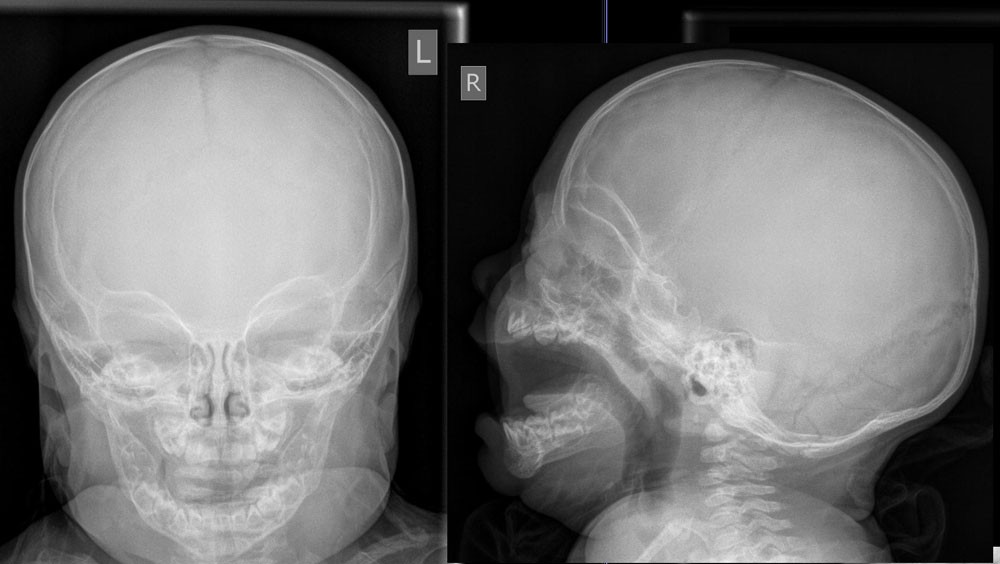

Schädel a.p.

Indikation zur Beurteilung von Verletzungen des Neurokraniums

• offene Schädelverletzung

• V.a. Impressionsfraktur

Nativdiagnostik bei Verletzungen des Neurocraniums umstritten - CCT empfohlen.

Schädel seitlich

CAVE

• Frakturnachweis (DD Suturen, Gefäßfurchen)

• Intrakranielle Luft (offene Schädelhirnverletzung)

• Frontobasis und Orbitadach

• Knöcherne Konturen der Sinus

• Spiegelbildung und/oder Verschattungen in den Sinus (Hämatosinus)

• Craniocervikaler Übergang (Abstand Atlasbogen und Dens axis) und obere HWS

• Knöcherne Konturen des Unterkiefers mit Kiefergelenk und Okklusion